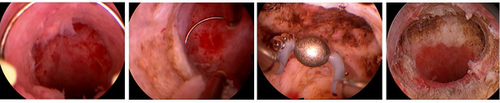

正常情况下女性做子宫憩室宫腔镜手术治疗的时间大概要三十分钟到六十分钟之间,具体与患者的病情严重程度有关系。子宫憩室就是在女性子宫下段切口处的肌壁有裂隙状缺损,严重者可能达到浆膜层。临床表现月经量多,经期延长,下腹可伴有腹部胀痛。